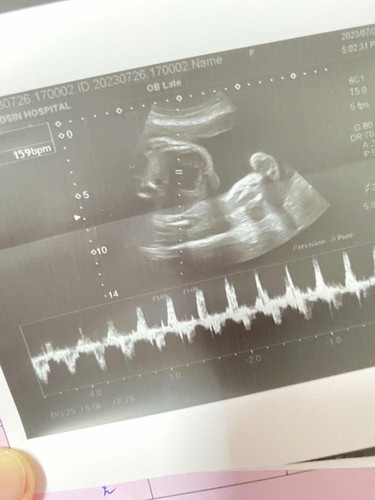

30w ท้องแรกลูกสาว

แม่ๆคะอันนี้ส่วนไหนของน้องบ้างคะดูไม่เป็นเลยค่ะน้องนอนคว่ำ